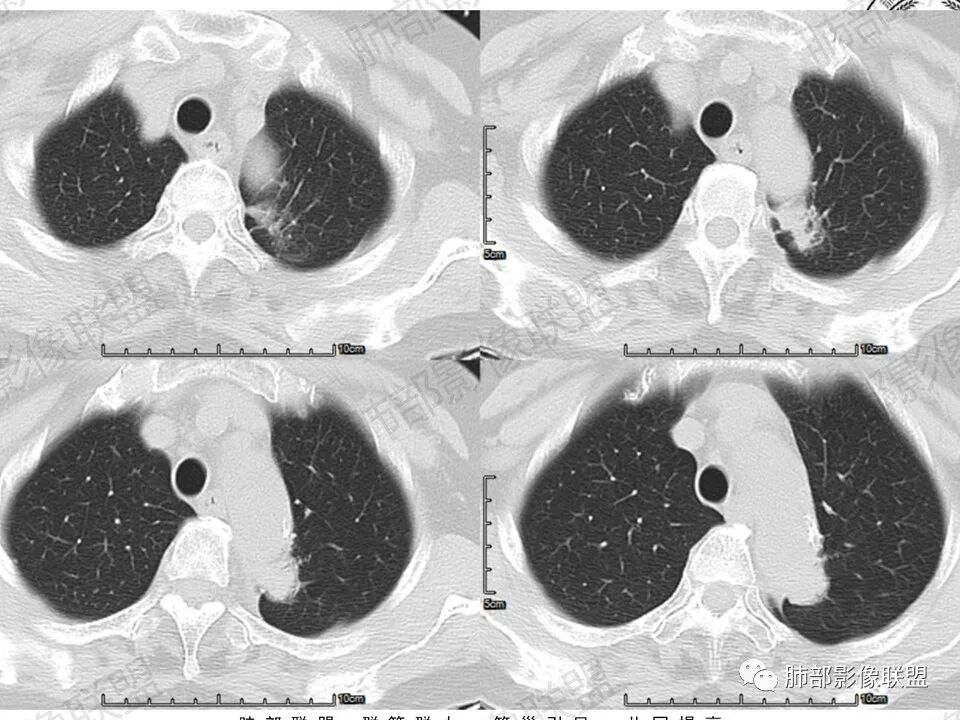

一、病例资料

病史无什么特殊性,老年女性。1、主动脉弓壁钙化2、长条影主要趴在弓部向胸主动脉位置。3、增强延迟明显强化,接近母血管。4、长形影周围条索影(纤维化)。敢在大血管长趴着睡的关系并接近强化,考虑主动脉假性动脉瘤?附壁血栓?周围局部包裹纤维化。

降主动脉旁不规则肿块,形态不规则,边缘平直,收缩,宽基底与主动脉相贴,周围脂肪间隙消失,病变内上缘可见支气管包绕?还是空泡?考虑肺内来源,病变平扫密度均匀,增强后动脉期低强化,静脉期和延迟期等同血管强化,局部血管壁增厚,上部可见主动脉发出血管供血,考虑1:肺隔离症2:炎性肉芽肿,3:腺癌

胸降主动脉旁片状软组织密度影,部分边缘欠规整,周围可见索条影,增强后均匀强化,并呈渐进性强化,考虑炎性肉芽肿性病变

降主动脉旁不规则肿块,形态不规则,宽基底与脏层胸膜相贴,局部胸膜掀起,增强渐进性明显强化,胸膜来源考虑STF,鉴别炎性肉芽肿病变病变

老年女性,左肺上叶纵膈旁不规则结节,可见局限性膨凸,边缘见磨玻璃成分,边界清晰,强化明显,考虑恶性,支持腺癌可能性大!

左肺上叶靠主动脉旁实性结节,宽基底相连,密度均匀,平直边及尖角,边缘长索条及胸膜牵拉,明显持续强化,考虑慢性炎症,鉴别腺癌

左肺上叶不规则肿块,与斜裂胸膜宽基相连、紧贴,斜裂增厚,增强持续、明显强化,并见血管穿行,边缘部分平直,部分膨隆,部分层面病灶边界不清,考虑慢性炎症,鉴别腺癌

主动脉旁软组织影,边界不清,内见含气支气管,周边不干净,考虑肺内来源病变,明显延迟强化,考虑慢性炎性肉芽肿病变,慢性炎症或结核。

老年女性,主动脉弓旁占位,宽基底与主动脉弓相贴,增强延迟均匀强化,内见血管穿行,周围见血管贴边,考虑胸膜来源肿瘤:SFT可能。鉴别慢性炎性病变

主动脉旁软组织影,边界不清 部分边缘平直,部分毛刺,内见血管影,周边不干净,考虑肺内来源病变,明显延迟强化,考虑良性病变,慢性炎症或IMT OP,鉴别腺癌。

老年女性。左上肺主动脉弓旁类椭圆形实性密度影,边缘有彭隆、局部平直,浅分叶;边界大部分清晰,少许须状影,少许边界清晰磨玻璃影;周围肺纹理欠干净,少许细线影;与临近胸膜面宽基底相连,一侧胸膜牵拉凹陷。增强后明显均匀强化。我考虑炎性病灶,建议抗炎治疗后短期复查,排除恶性可能。少许的磨玻璃让人心慌,腺癌也是很有可能,主要就是持续的明显强化,不太符合。

左肺上叶尖后段主动脉旁结节影,病灶紧贴主动脉,分界清,增强扫描渐进性强化,内见血管影,考虑慢性炎性病变。鉴别SFT.

老年女性,体检发现左上肺主动脉弓旁占位,脂肪间隙清晰,边缘部分光滑、部分毛糙,似有毛刺、分叶,似有边界清楚的GGO,内部大部密度均匀,有条索状低密度(支气管粘液栓?),增强检查见均匀明显强化,延迟强化明显(CT值增加近80Hu)。边缘见支气管提示肺内病变。整体考虑炎性可能,炎性病变的强化似乎是以动脉期明显,本例延迟强化明显,延迟强化明显的病例可能有:PSP、类癌、淋巴上皮瘤样癌、炎性病变?…………似有分叶及病灶边缘GGO,注意鉴别腺癌。

临床,眼科入院常规,肺部无症状,慢性炎症或恶性偷袭。视物变形,黄斑裂空可以解释,颅内不一定有问题,常规眼部ct,以防万一。定位,肺内血管进入,外缘毛糙,有肺纹进入,肺内的可能大。影像:    良性征像, 1、 病灶紧贴主动脉的细、长条状,炎性的王牌。2  、有直边、多边征 3、 矢状位略成梯形,垂直主动脉弓。  恶性征像较多,但多位低权重征像部分似是而非:1 主动脉弓后缘动脉壁似有侵袭 2  斜裂有轻度收缩 3 内上似见一个月牙铲 4 实性病灶周围有境界清晰的磨玻璃影  5 有小叶间隔阻挡现象 6 血管造影征?7 病灶略有膨隆 。中立征像:持续高强化,可以见于1 腺癌 、2 纤维类肿瘤 3肉芽肿病变。综上 1 腺癌第一(伴粘液腺)2 炎性肉芽肿待除外

入院检查发现的左肺上叶软组织密度影,定位左肺上叶胸膜下近主动脉处,未见明显分叶和毛刺,增强CT显著强化,周围见血管环绕,内部未见血管和支气管充气征。考虑肉芽肿炎性病变,强化明显肿瘤可能小,建议抗感染后复查,暂无活检或手术指征。

2.轴位显示主动脉弓旁依势傍行弧形高密度影,隐约见尖后段支气管进入并截止。病灶边界较清楚,见血管结构及线性影与邻近肺组织相延伸。

3.病灶渐进性显著均匀强化!动脉期未见主动脉腔异常通道。